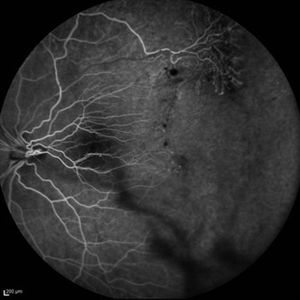

Behcet's Disease Behcet's DiseaseMar 13 2013 by Hamid Ahmadieh, MD Early phase FA of the left eye of a 23-year-old man with retinal vasculitis due to Behcet's disease . Photographer: Solmaz Shahmohammad, Negah Eye Center, Tehran Imaging device: Heidelberg Spectralis Condition/keywords: retinal vasculitis